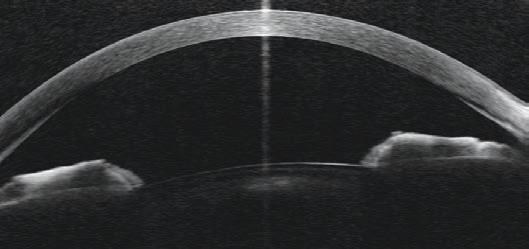

HP-OCT OFFERS ‘PARTICULAR ADVANTAGES IN THE ANTERIOR SEGMENT’

Cylite is an Australian-based company developing the next generation of diagnostic OCTs for optometry and ophthalmology. The company’s Hyperparallel OCT (HP-OCT) is a world-first, capturing accurate volumetric data of the eye, with particular advantages in the anterior segment.

“Scanning at an industry-leading 302,400 A-scans per second, the technology simultaneously images across a wide area of the eye with minimal motion artefacts, allowing the production of highly accurate and repeatable elevation and curvature maps, as well as accurate analytics to enable clinicians to make more informed decisions for better patient outcomes,” Cylite states.

According to the company, in one scan, the HP-OCT captures a full 3D image of the anterior segment, which can be used for personalised contact lens fitting, as well as a full set of biometric measurements, including axial length, for use in myopia management. The same volumetric imaging technique can also be applied to the posterior segment to produce excellent volumetric retinal images.